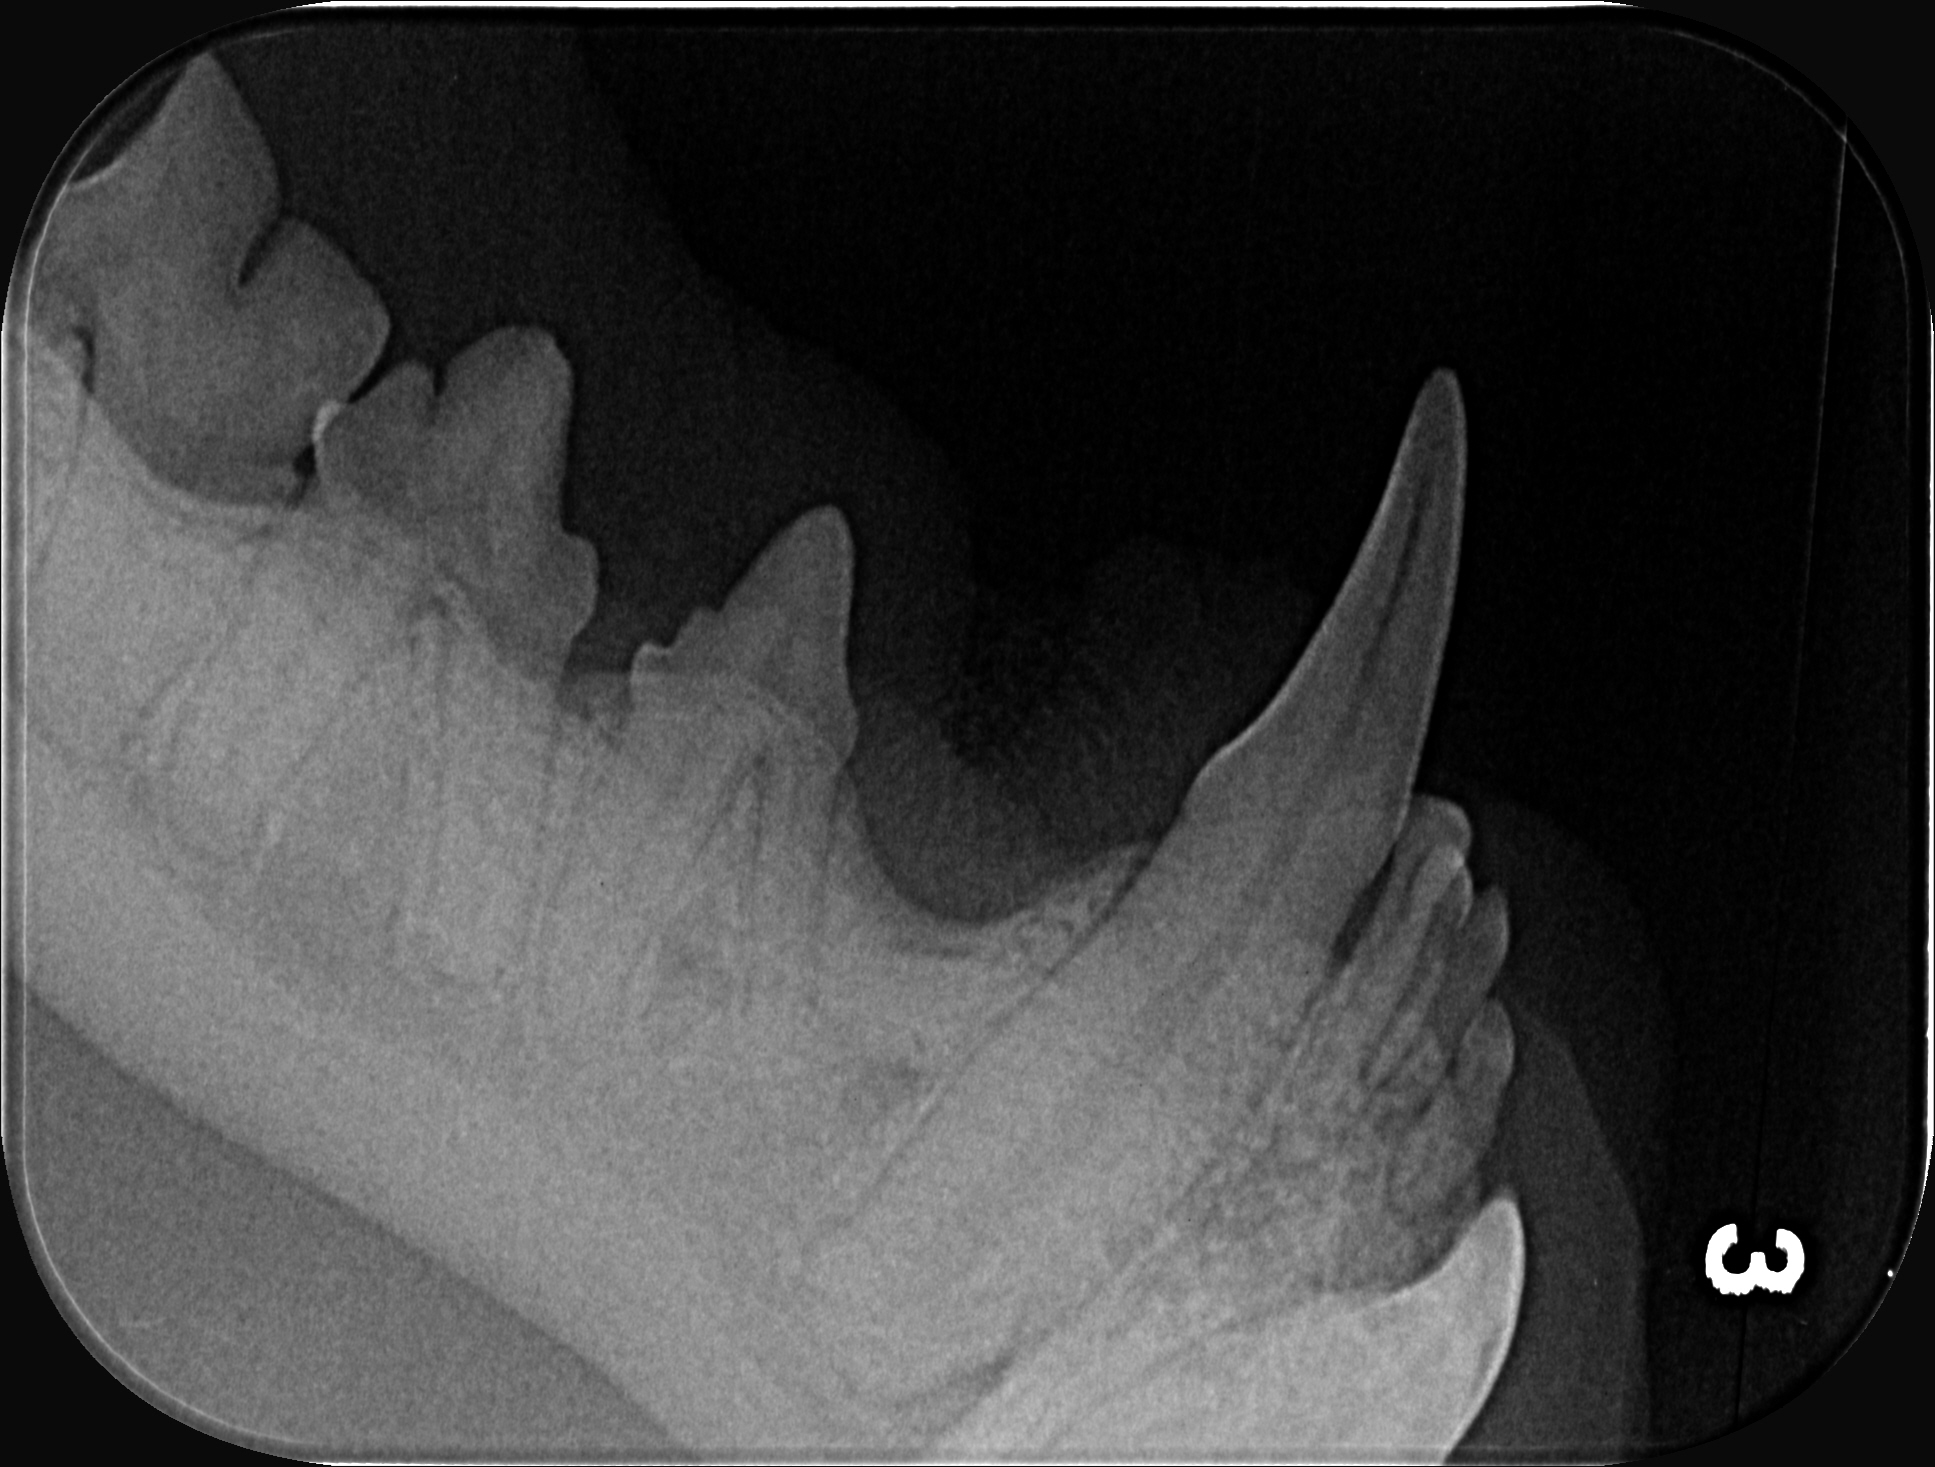

Und dann kam die Untersuchung. Und dann kam das Thema Zahnsanierung.